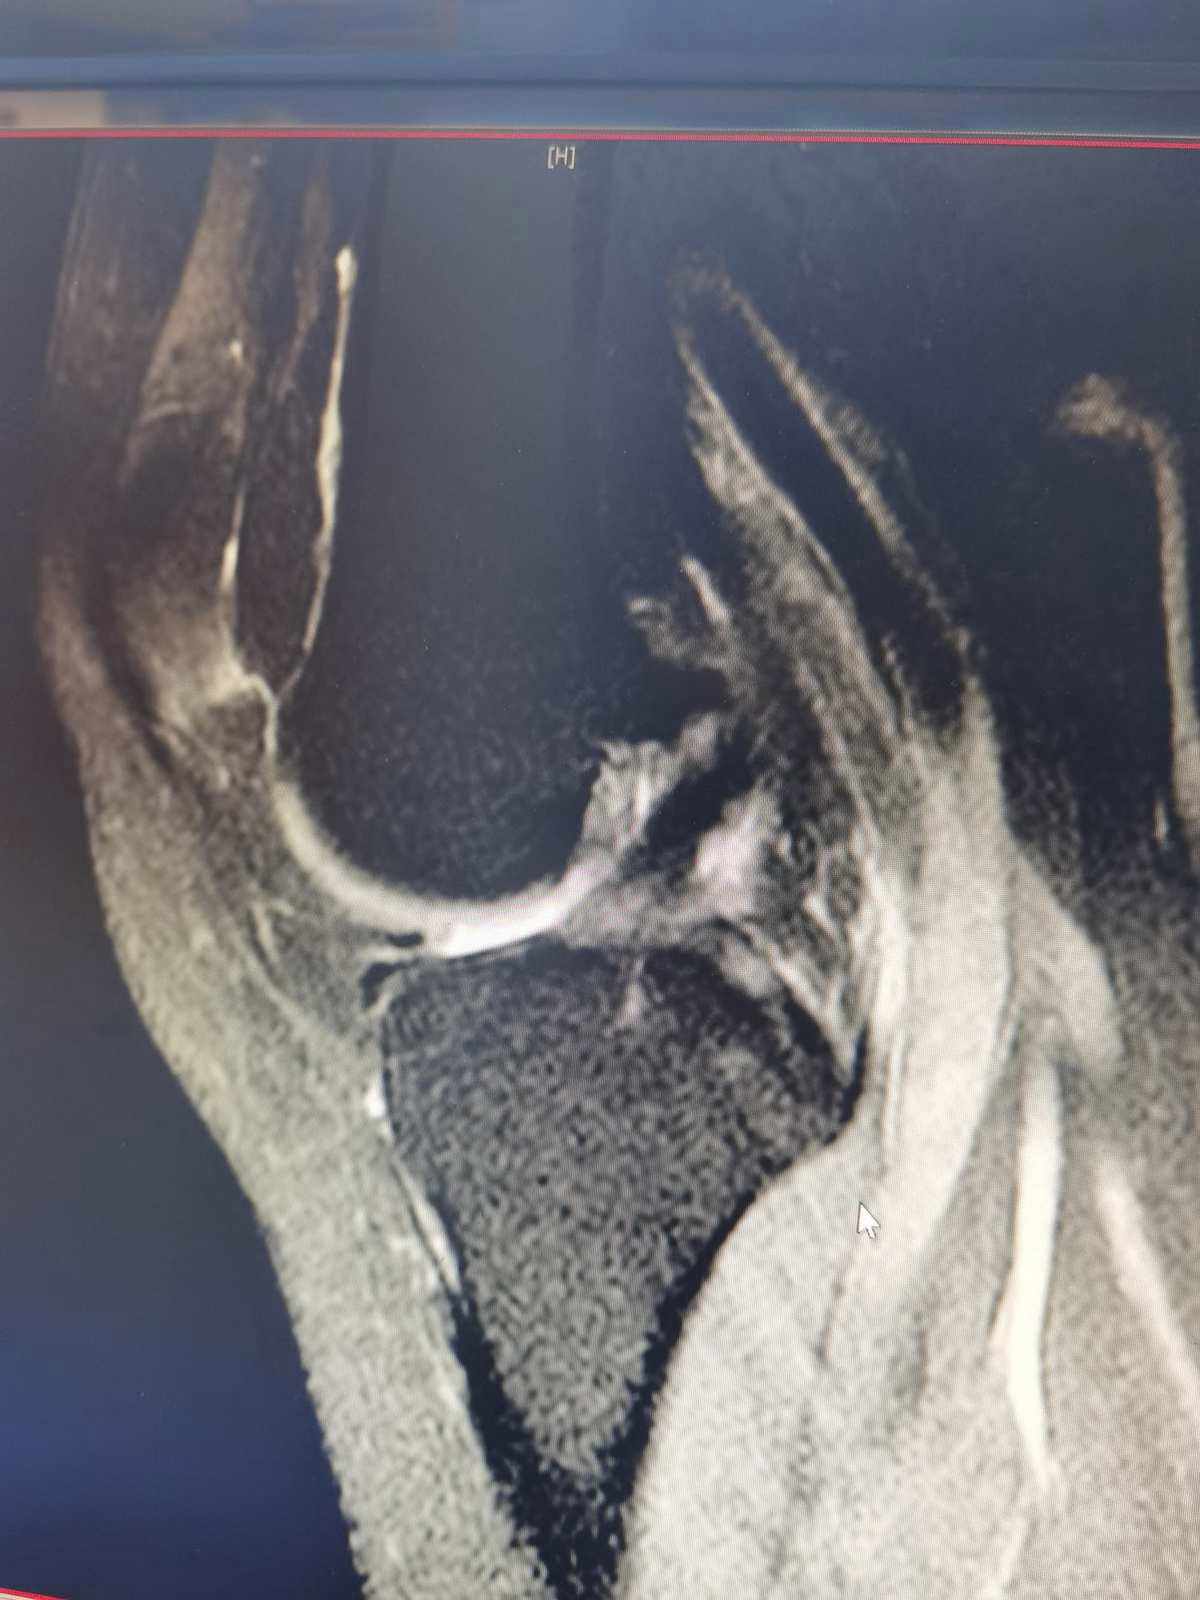

影像学检查:前交叉韧带损伤的确诊通常需要进行MRI、X光等影像学检查,MRI检查可清晰显示出前交叉韧带的破裂情况及其他并发损伤。但是由于出血等因素可能会引起膝关节肿胀,可能出现伪影影响诊断。